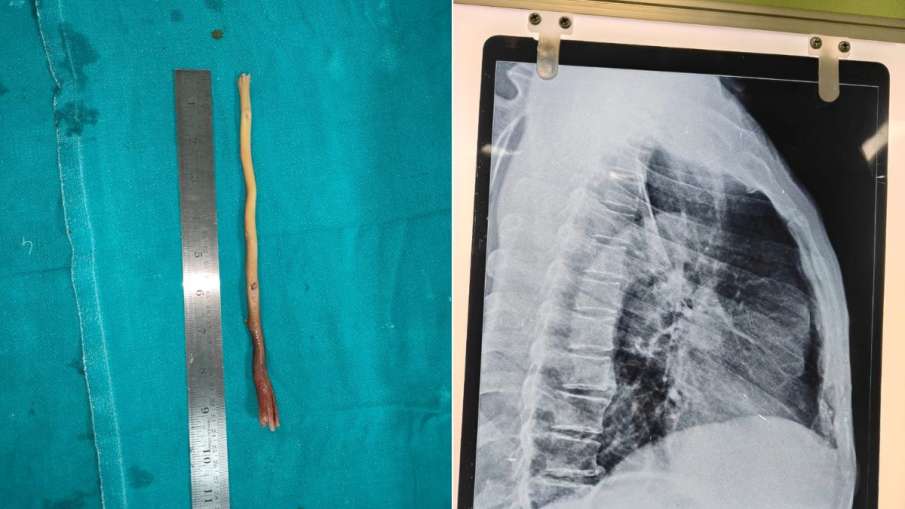

बुजुर्ग की भोजन नली में फंसा था 9 इंच का दातून

डॉक्टरों ने ऑपरेशन कर दातून को बाहर निकाला।

डॉक्टरों की 9 सदस्यीय टीम ने ‘एसोफोगास्कोपी’ नाम की एक तकनीक का इस्तेमाल किया। इस प्रक्रिया में गले के अंदर एक खास ट्यूब डाली जाती है जिससे अंदर की चीजों को देखा और निकाला जा सकता है। इसी ट्यूब के जरिए धीरे-धीरे दबाव बनाकर दातून को बाहर निकाला गया। ऑपरेशन पूरी तरह सफल रहा और अब कामराजू नायक पहले से बेहतर महसूस कर रहे हैं।